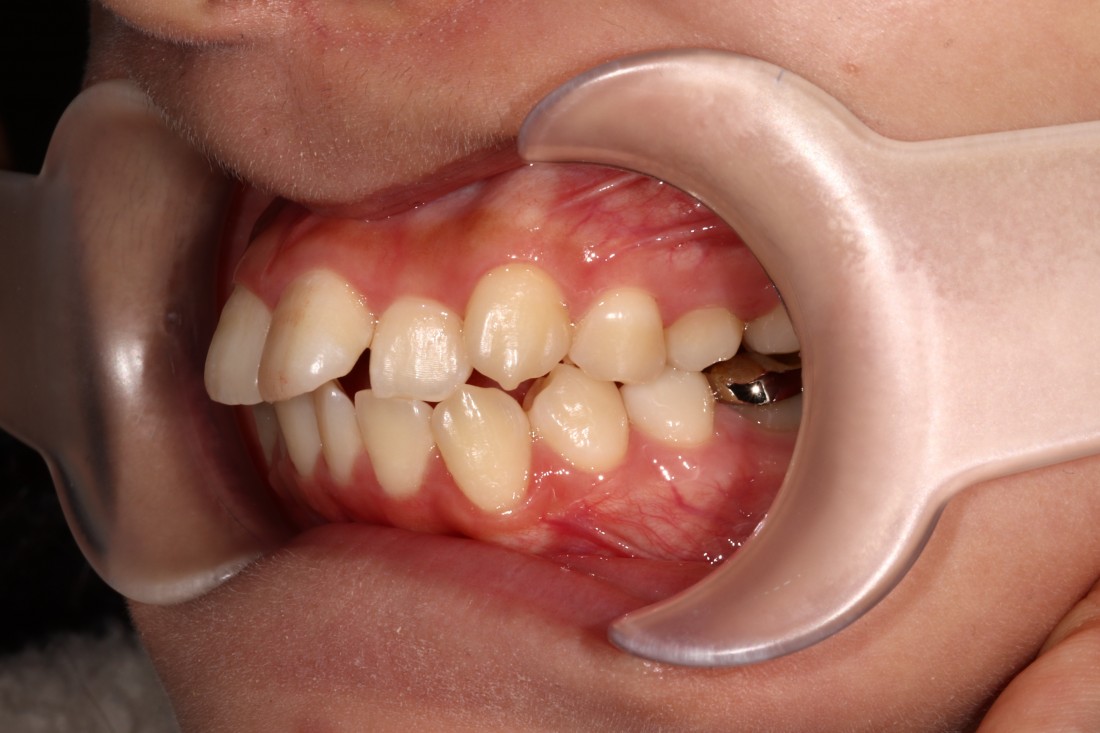

광주 성인 교정치과에서

충치치료와 교정진료를 동시에 받으신

성인 여성 환자분의 케이스입니다.

충치치료 전에는 은색 보철물이 있던 자리에

교정진료의 마무리와 동시에

치아색 보철물을 씌워서

치아교정 + 충치치료를 동시에 진행하였습니다.

광주 성인 치아교정의 경우

충치치료의 시기를 잘 판단하여

성공적인 진료를 완성할 수 있기 때문에

분과별 전문의가 협진하는

광주 성인 교정치과를 선택하시는 것이 좋습니다.